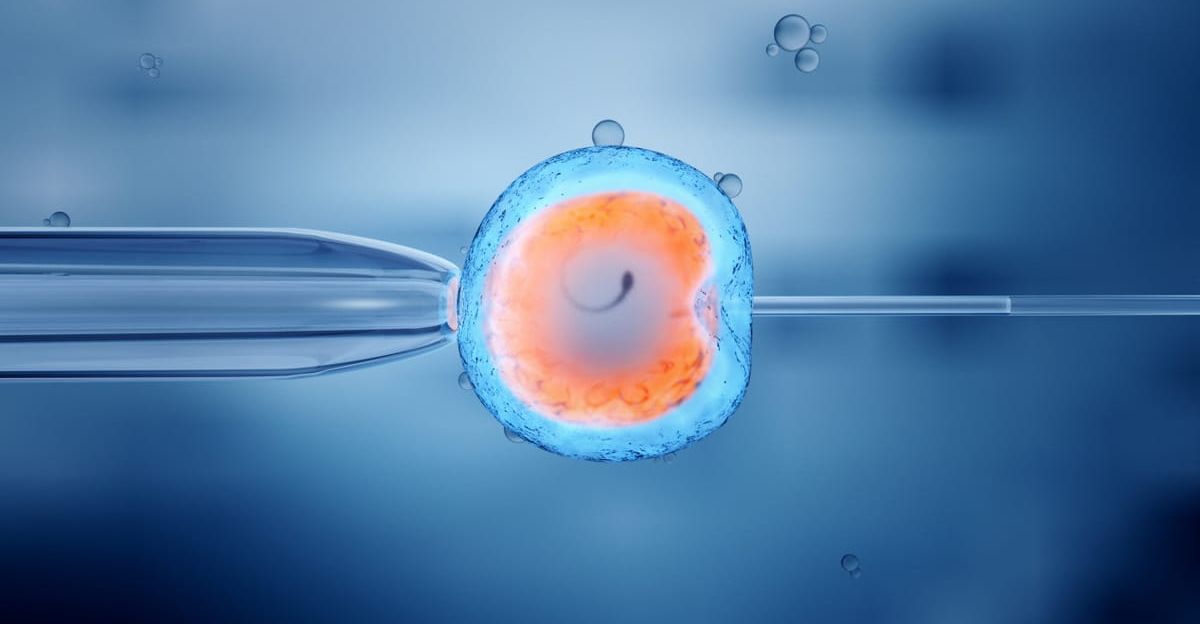

Since 1990, UK clinics have been able to test embryos for serious genetic disorders—Huntington’s disease, cystic fibrosis, and sickle cell disease. The law reflects a principle: testing should prevent suffering, not improve traits.

The HFEA, the independent regulator, has enforced this for 30 years. Polygenic risk scores—predictions of intelligence or height from thousands of genetic variants—are explicitly banned.

They lack proven validity, involve multiple genes with tiny effects, and risk eugenic discrimination. The framework prevents a genetic hierarchy in which only the wealthy have access to superior embryos.

Herasight, a US biotech company, enables couples to submit their embryos’ genetic data and receive predictions for IQ, height, and disease risk across various conditions.

The company charges $50,000 per couple for unlimited embryo assessment. It claims selecting from five embryos using its algorithm yields an average 6-point IQ gain—the largest documented embryo selection effect if true.

The European Society of Human Genetics condemned polygenic embryo screening as “unproven and unethical.”

The criticism focuses on three problems: (1) polygenic scores work best for specific populations and lose accuracy across different ancestries; (2) environment heavily influences intelligence and height, weakening predictions; (3) ranking embryos using these scores means enhancement, not disease prevention.

Herasight’s 6-point IQ gain claim is extraordinary by scientific standards, yet the company never published peer-reviewed proof. Couples pay $50,000 based on company claims, not research. Regulators watch whether this spreads.